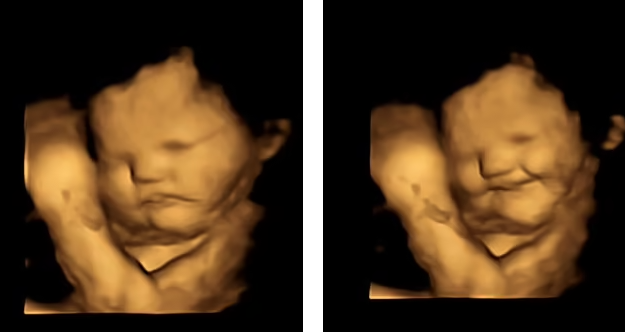

وأظهرت النتائج كيف ابتسم الجنين بعد فترة وجيزة من أكل الأم للجزر، على العكس مما فعل عند تناول الكرنب.

وأظهرت النتائج، أن كمية صغيرة فقط من نكهة الجزر أو الكرنب كانت كافية لتحفيز تفاعل الأجنة. وعندما تناولت النساء الجزر، كانت الأجنة تميل إلى الابتسام عند الفحص، بخلاف رد فعلهم عند تناول كبسولة الكرنب، حيث كانت تميل إلى التجهم.

قالت المؤلفة الرئيسية بيزا أوستون: "كان من المدهش حقًا رؤية تفاعل الأطفال الذين لم يولدوا بعد مع نكهات اللفت أو الجزر أثناء الفحص ومشاركة تلك اللحظات مع والديهم".